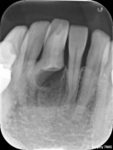

「陥入歯」とは、歯の頭の部分の表層のエナメル質と内部の象牙質が神経のお部屋の中(歯髄腔)にさまざまな程度で陥入している形態異常の歯のことです。少し難しい説明になってしまいましたが、簡単に言うと、歯が作られる過程で陥入することによって形態異常を起こしてしまった歯のことです。歯の中にもう一つ歯ができているように見えることから「歯内歯」と言われたこともありましたが、現在では歯の発生の概念から、歯の外側のエナメル質が内側の象牙質に折り込まれてデッドスペースを形成していると考えられ「陥入歯」として統一されています。

1957年にOehlersは「陥入歯」を以下3つタイプに分類し、現在もこの分類が広く用いられています。従来のOehlersの分類では、歯軸方向への陥入の程度によって3つに分けられていましたが、タイプⅢにおいては、歯根側面に貫通するもの(Ⅲ-a)、根尖に貫通するもの(Ⅲ-b)の2つに分けられ、近年では4つの分類として用いられることが多くなりました。

TypeⅠ:陥入が歯冠部にとどまり、セメントエナメル境(CEJ)を越えないもの。

TypeⅡ:陥入がCEJを越えて歯髄腔内におよぶが、歯周組織との交通がなく、根管内にとどまるもの。

TypeⅢ:陥入が側方の歯周組織(Ⅲ-a)または根尖(Ⅲ-b)に貫通しているもの

Ridellらの文献では、TypeⅠが79%、TypeⅡが15%、TypeⅢが5%と報告されています(※2)。また、好発部位は上顎前歯部と言われています。